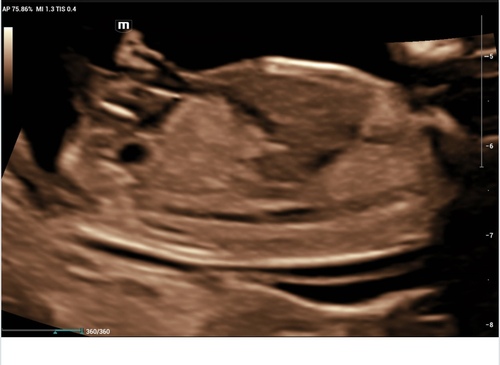

Echo met 14 weken. Wat denken jullie🩷🩵?

Wat denken jullie 14+1